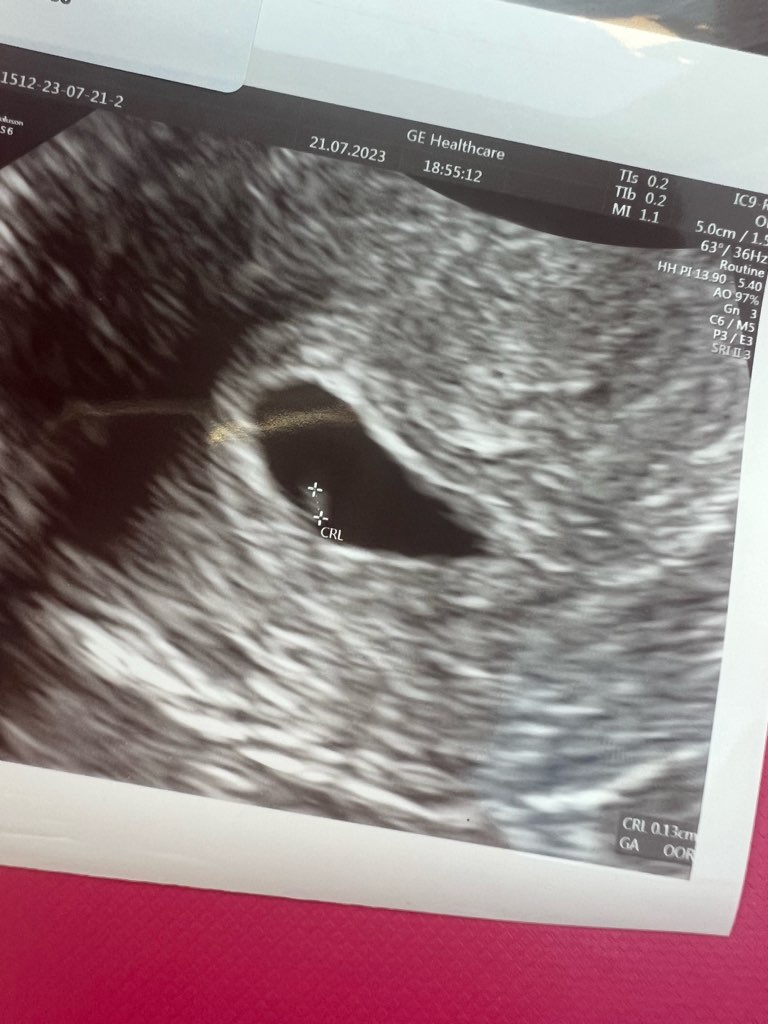

Jest pęcherzyk 0,99cm, ciałko żółte 0,33cm i malusieńki zarodek 0,13